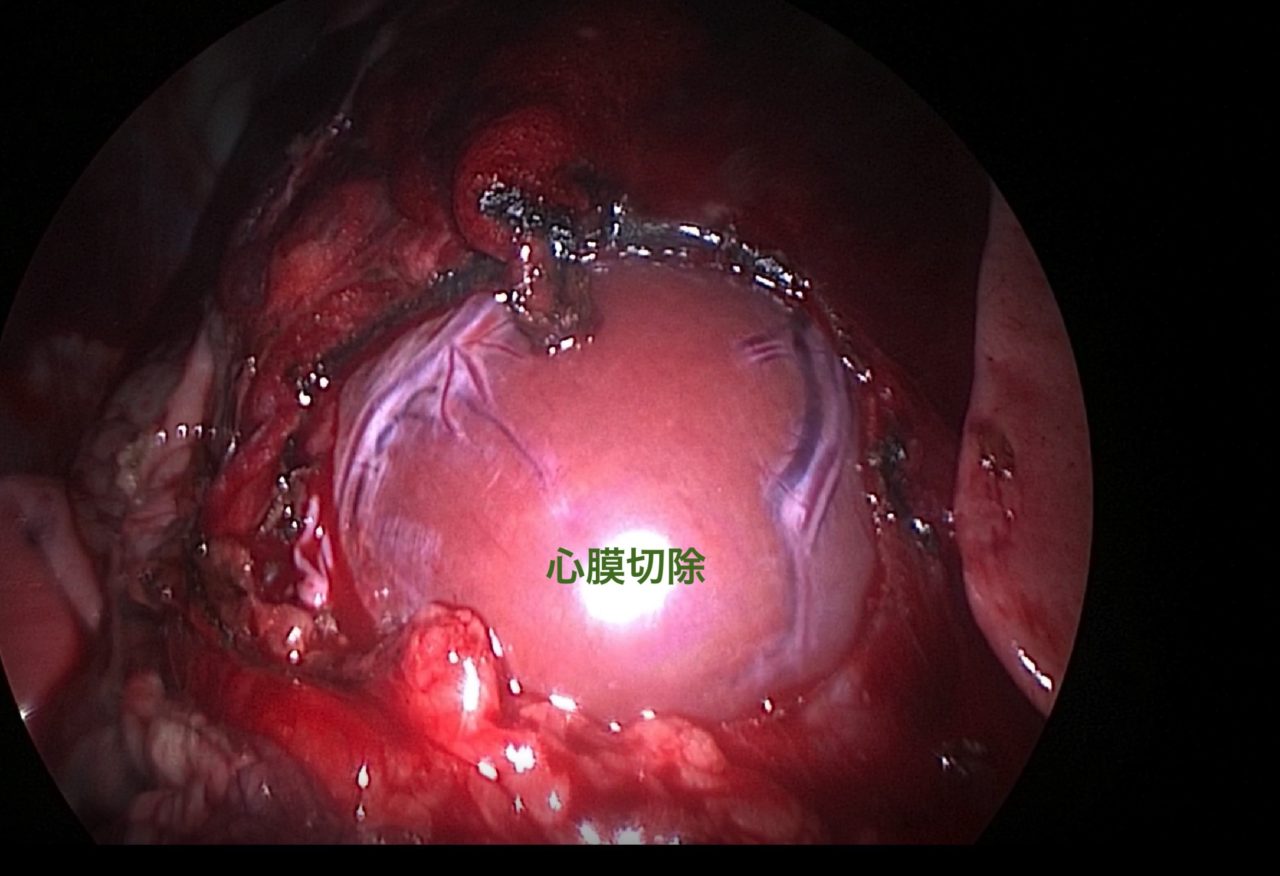

ゴールデンレトリバーは血管肉腫の好発犬種です。特に右心耳、肝臓、脾臓などに発生する事が知られています。右心耳であれば心タンポナーデという状態を引き起こし、循環状態が悪化し低血圧となり突然倒れてしまいます。聴診でマッフルサウンド、心電図では電気的交互脈、胸部エックス線ではムーンハートを呈しています。超音波で拡張期に右心房が虚脱する様子が確認されます。心嚢内圧を下げるために、直ちに心膜穿刺術で救命を行います。残念ながらこの腫瘍に対する根治的な治療方法はなく、進行すれば再発性の出血性心タンポナーデを何度も繰り返す(何度も倒れる)ことになります。そこで、姑息的な手段ですが心膜切除術を行なっておけば心タンポナーデを回避する事が出来ます。近年、テクノロジーの発展とともに開胸術ではなく胸腔鏡を使って小さな傷で手術を行う事が可能となっています。この病気は突然ワンコを襲い、見つかった時はすでに進行している事がほとんどです。だからこそ、最小侵襲で最大の効果が期待できる胸腔鏡下心膜切除術に真の価値があると言えます。開胸術に比べ痛みも少なく入院も短くて済むからです。我々はたとえ根治不能な病気であっても、患者さんがQOLを保ちながらご家族との大切な時間を1日でも長く過ごせるように、チームで話し合いながら”より良い”を常に模索し続けます。